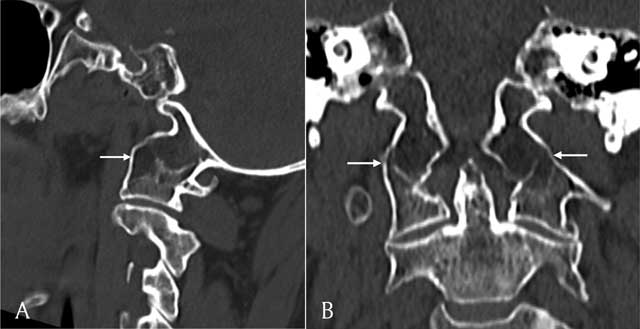

Figure 4

Sagittal (A) and coronal (B) reconstructions of a CT scan of the cervical spine shows assimilation of the massa lateralis of C1 and the occipital condyle (white arrows).